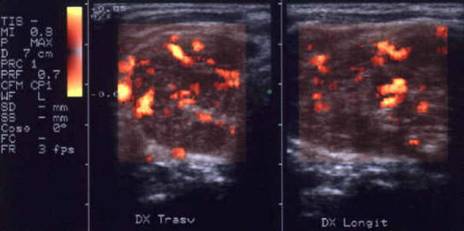

CarcinomUL papilar

Lobul drept, proiectie trasversala si longitudinala.

Femeie de 29 ani. Nodul de consistenta dura in lobul

drept si istm.

Ecografia: nodul cu margini difuze in lobul drept si istm, care deformeaza

conturul anterior al glandei, structura parenchimatoasa, neoomogena, hipoecogena.

Prezenta de linfonoduli laterocervicali.

Citoaspiratia: carcinom papilar.

Examen histologic: carcinom papilar plurifocale varianta foliculara.